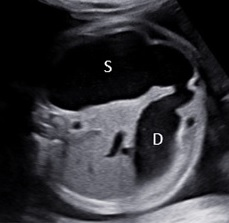

Siêu âm bé sau sinh tại bệnh viện Nhi đồng 1 ghi nhận ở vùng sau phúc mạc bên trái có một khối không đồng nhất kích thước: 53x81x75mm với hình ảnh vòm sọ, cột sống, mô mở và xương dài bên trong và đẩy thận trái xuống hố chậu. Siêu âm chẩn đoán: Thai trong thai.

Hình 5: Siêu âm em bé sau sinh, ở sau phúc mạc và trên thận có một khối không đồng nhất với hình ảnh vòm sọ (dấu sao) và cột sống (mũi tên)